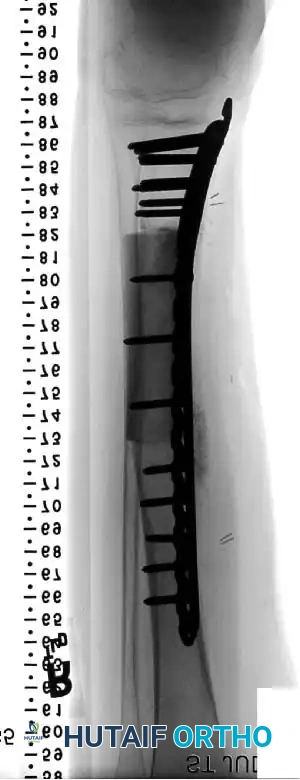

Advanced Reconstructive Modalities and Distal Extensions

While proximal humeral resections dominate shoulder oncology, tumors extending into the humeral diaphysis or distal humerus require equally complex limb salvage strategies. Total humeral replacement or distal humeral megaprostheses are viable options when the radial nerve can be preserved or grafted.

Intraoperative Imaging and Margin Assessment

Continuous intraoperative assessment using fluoroscopy and frozen section pathology is mandatory. The following images demonstrate various stages of complex upper extremity resections, allograft preparations, and prosthetic implantations across the humerus and elbow joint.

Distal Humerus and Elbow Reconstruction

When tumors involve the distal humerus, resection often requires sacrifice of the collateral ligaments and the articular surface of the elbow. Reconstruction is typically achieved using a linked, semi-constrained total elbow arthroplasty designed for oncologic defects.